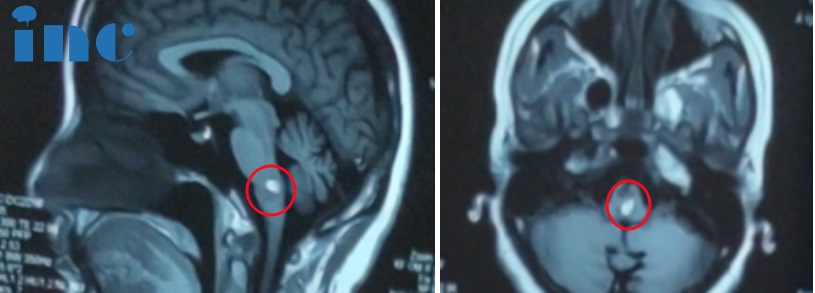

2016年1月4日,再次住院,入院诊断:脑出血。入院情况及治疗经过:患者因“突发头痛伴左侧肢体无力6天”入院,入院查体左上肢肌力Ⅱ级,左下肢力Ⅲ级,左侧肌张力增高;右侧肢体肌力、肌张力正常‘左侧腱反射大于右侧。左侧偏身痛温度觉减退,颈软。头部核磁示:延髓腹侧出血,多考虑为海绵状血管瘤伴出血所致。

2023年8月20日左右,症状又开始加重,这时右手也出现了麻木的症状,核磁显示再次出血。